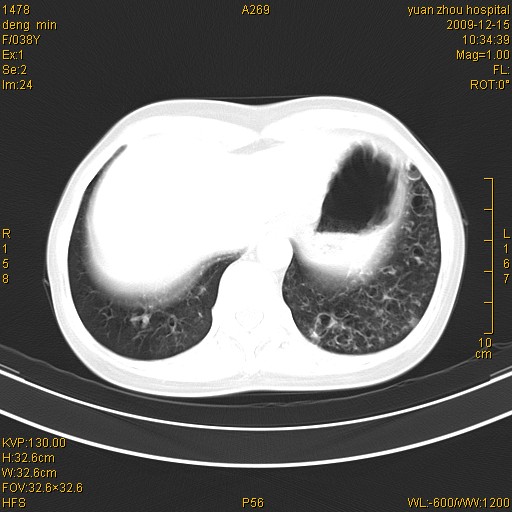

标题: CT23919:F38Y 咳嗽月余 [打印本页]

标题: CT23919:F38Y 咳嗽月余

支扩并感染

支气管扩张。典型。

右肺中下叶、左肺上叶舌段及左肺下叶支气管扩张合并感染。